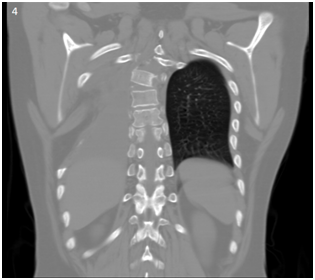

During a soccer game, the patient suffered a trauma to the thoracolumbar region. It started with pain in the same area, and outpatient treatment was based on NSAIDs with partial improvement. Two days after the incident the patient started with cough of nocturnal predominance, insidious onset, in long accesses, without expectoration, and without apparent trigger. His is evaluated in the ER triage area with clinical examination and X-ray. The relevant data in physical examination includes: thoracic scoliosis with deviation to the right, decreased amplexation, decreased respiratory sounds in right hemithorax region. The patient had pain on palpation in spinous processes T4, T5, T6. The chest x-ray revealed the absence of 5, 6 and 7 right costal arcs with dorsal dextroescoliosis (Figures 1A and 1B). No fever or other clinical data was given, and the patient was discharged with alarming symptoms and Ibuprofen.

<strong>Figure 1A </strong> Chest X-ray with absence of 5,6 and 7 right costal arcs with dorsal dextroescoliosis.

Figure 1A Chest X-ray with absence of 5,6 and 7 right costal arcs with dorsal dextroescoliosis.